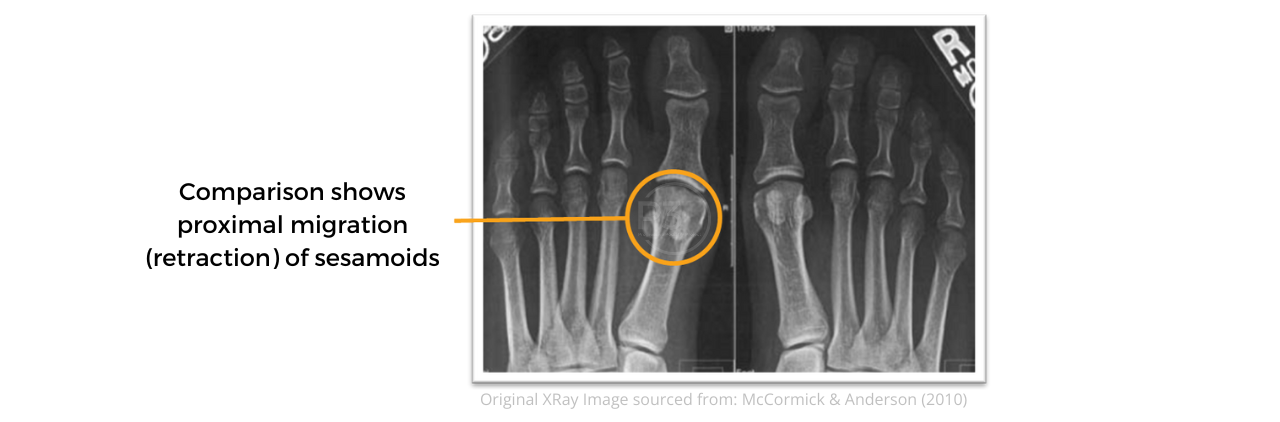

Should you refer for plain radiographs, obtaining comparison films are encouraged, as this can identify proximal migration (retraction) of the sesamoids in higher-grade plantar plate injuries in AP view. (Hainsworth & McKinley, 2018).

Proximal Migration (retraction) of the Sesamoids | © P3Podiatry